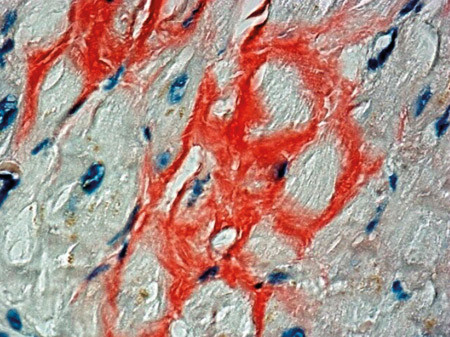

Transvenøs biopsi av endomyokard viste avleiring av amyloid (fig 2), der immunohistokjemisk fremstilling avdekket nedslag av transtyretin (prealbumin) (fig 3).

Amyloidose er en tilstand karakterisert ved nedslag av monomorft proteinmateriale i ett eller flere vev. Dette materialet gir et karakteristisk «eplegrønt» skimmer når det farges med kongorødt og betraktes i polarisert lys. Flere naturlig forekommende og muterte proteiner har evnen til å danne amyloid. Etter molekylærbiologiske fremskritt kan man nå skille mellom en rekke typer amyloidose ut fra hvilket protein som felles ut (6). De viktigste systemiske formene for amyloidose er amyloid lettkjede (AL)-amyloidose (tidligere kalt «primær» amyloidose), forårsaket av nedslag av lette kjeder ved monoklonal plasmacelleproliferasjon, og amyloid A-protein (AA)-amyloidose («sekundær» amyloidose). Ved sistnevnte er det nedslag av et leversyntetisert akuttfaseprotein ved langvarig inflammatorisk tilstand (6).

Den vanligste form for kardial amyloidose er imidlertid amyloid transtyretin (ATTR)-amyloidose, også kalt senil systemisk amyloidose. Denne formen for amyloidose forårsakes av utfelling av transtyretin (tidligere kalt prealbumin) (7). Prevalensen av slik amyloidose i autopsimaterialer hos eldre er angitt å være ca. 25 % (8). Langt de fleste tilfeller er asymptomatiske. Selv symptomgivende kardial ATTR-amyloidose har langt bedre prognose enn f.eks. AL-amyloidose, med en forventet levetid på 5–6 år versus under 12 måneder (9).

Kardial amyloidose medfører ofte EKG-forandringer, mest typisk ses små elektriske amplituder i standardavledningene (low voltage). Funnet er imidlertid ikke patognomonisk (9) og fantes ikke hos vår pasient. Ekkokardiografisk ses fortykkelse av myokard med typisk ekkogenisitet og restriktivt fyllingsmønster (10). For sikkert å kunne stille diagnosen kreves imidlertid biopsi – ved systemisk sykdom kan biopsi tas fra rectum eller abdominalt fettvev. Imidlertid er sensitiviteten ved biopsi i ekstrakardialt vev lav ved ATTR-amyloidose (9).

Hos vår pasient fant man betydelig nedslag av transtyretin i myokard. Dette ses ved to tilstander: Ved arvelig sykdom forårsaket av mutasjon i genet for transtyretin, noe som gir hjertesvikt og polynevropati i relativt ung alder, og ved senil systemisk amyloidose, der det utfelles «villtype» (normalt) transtyretin. Denne tilstanden gir kardial amyloidose i høy alder, vanligvis uten sikre symptomer (7). Vår pasient hadde verken nevropati, sykdomsdebut i ung alder eller familiær forekomst av amyloidose eller uforklart hjertesvikt. Vi fant det derfor sannsynlig at han hadde den vanlige, ikke-arvelige varianten av amyloidose med nedslag av normalt transyretin. Det ble ikke gjort elektroforese eller genetisk testing med tanke på ev. mutasjon, da slik diagnostikk ikke utføres i Norge.